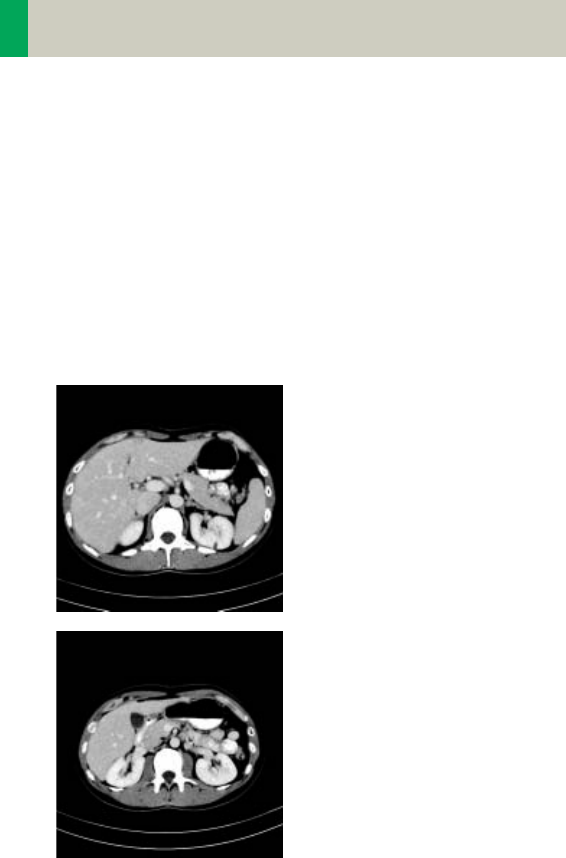

Abdomen

AbdomenRoutine/

AbdomenRoutine08s

Indications:

Spiral mode for all routine studies in the region of

abdomen, e.g., evaluation, follow-up examinations

etc.

A typical abdomen scan in a range of 20 cm will be

covered in 16/13 sec.